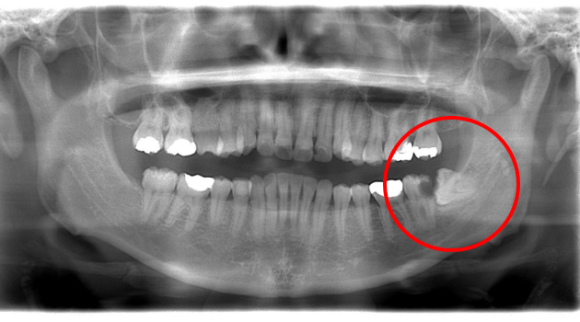

親知らずは一番最後に生えてくるため、生えてくる場所が残されていません。

その為に骨の中に埋まったまま出てこなかったり、横や斜めに生えてきて多くの障害を引き起こします。

親知らず画像 親知らずの多くは無症状に悪さを引き起こします。まさにトラブルメーカーです。